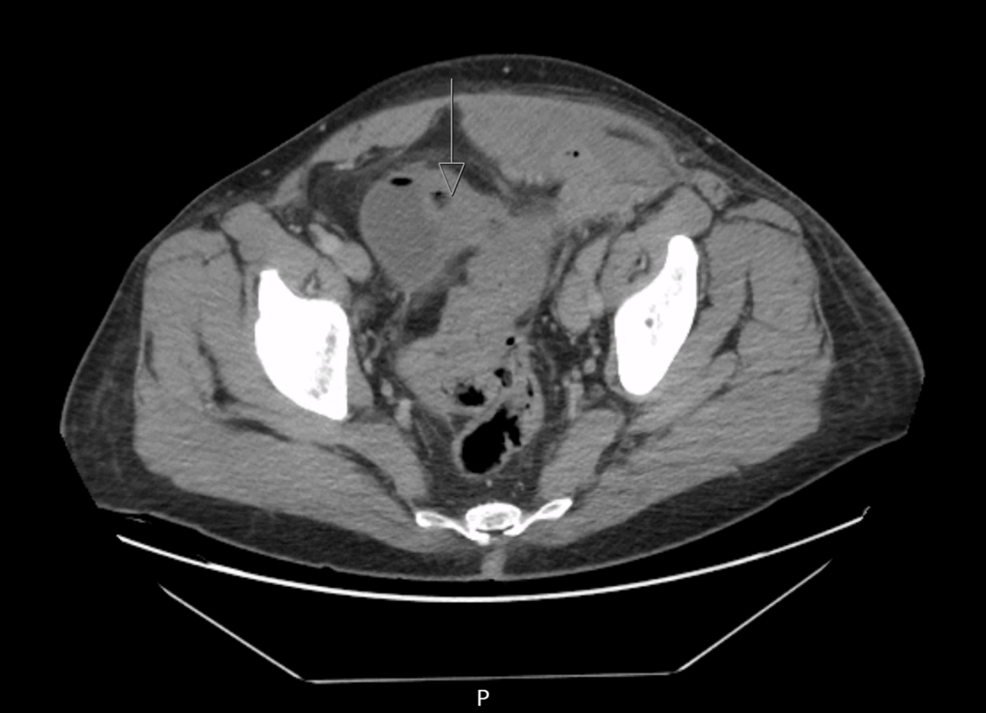

Un reciente reporte de caso publicado en Cureus detalla el tratamiento exitoso de una diverticulitis agresiva complicada con fístulas colovesicales y cutáneas mediante la realización de una colostomía para la desviación intestinal. La diverticulitis, una inflamación o infección de pequeñas bolsas que pueden formarse en el revestimiento del intestino grueso (divertículos), puede volverse severa y provocar complicaciones como estas fístulas, que son conexiones anormales entre el colon y la vejiga (colovesical) y la piel (cutánea).

El caso presentado describe a un paciente que requirió una colostomía para permitir la curación de las fístulas y controlar la inflamación. La colostomía, un procedimiento quirúrgico que crea una abertura en el abdomen para desviar el contenido intestinal, permitió que el intestino se curara y redujera la contaminación causada por las fístulas. Este enfoque quirúrgico es una opción importante en el manejo de casos complejos de diverticulitis con complicaciones graves.